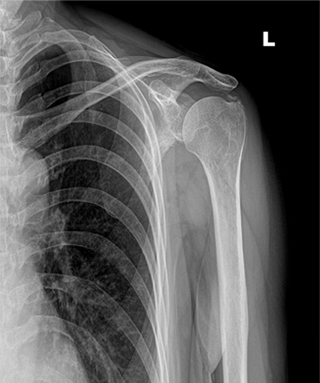

체외충격파 치료 후